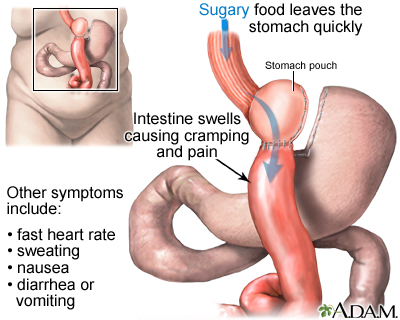

Khoa Dinh dưỡng, Bệnh viện Hữu nghị đa khoa Nghệ An Hội chứng dumping là rối loạn tiêu hóa xảy ra khi thức ăn di chuyển quá nhanh từ dạ dày xuống ruột non sau ăn, gây ra nhiều triệu chứng khó chịu về tiêu hóa và tuần hoàn. Hội chứng này thường gặp sau […]